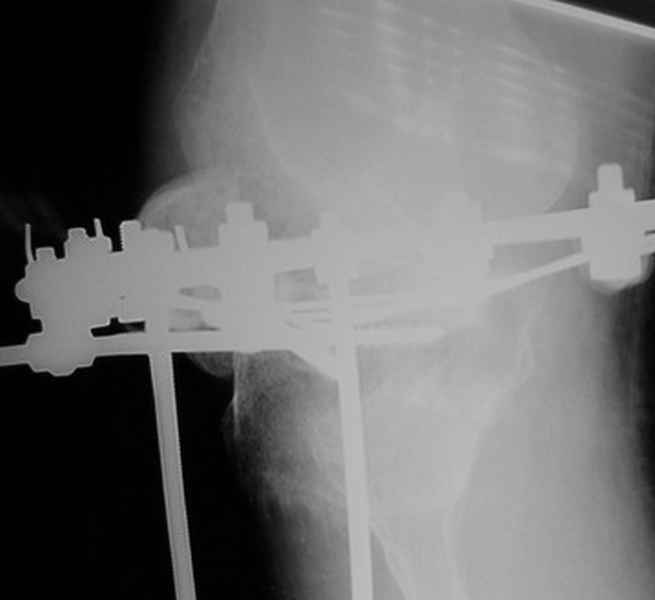

Пациент В. 53 лет, травма в феврале 2009. ДЗ. Открытый оскольчатый перелом нижней трети голени. При боли поступлении выполено ПХО, аппарат Илизарова. В последующем проводили ВХО, резекция костных отломков, укорочение 6 см, рана зажила. Была выполнена остеотомия большеберцовой кости в проксимальном отделе, резекция. Производилось тракция. На последних рентгенограммах выявлено, что одновременно с "выращиванием" регенерата произошло низведение надколенника на длину выращенного регенерата. Клинически: активное разгибание сохранено, объем движений в колене 180-110 градусов. Черными стрелками обозначен верхний край надколенника с одной и с другой стороны. Красная стрелка обозначает пальпируемую связку надколенника. Причина - остеотомия выше места прикрепления связки надколенника. Вопрос: была ли у кого подобная ситуация? Что делать? При первом обдумывании приходит решение: отсечение места прикрепления связки надколенника с костным блоком, перемещение на "правильное" место, укорочение сухожилия четырехглавой мышцы.

В прошлом сообщении вы писали, что разгибание - 180 градусов, поэтому я и считаю, что срок в два месяца не является критичным и активное разгибание после перемещения места прикрепления собственной связки надколенника восстановится быстро. Ведь ни рубцового перерождения, ни укорочения мышц на бедре не было.

По снимкам - плотность регенерата хорошая, сложностей с фиксацией в него костного "основания" быть не должно.

К сожалению, подобное осложнение "нет-нет да и возникает" при удлинении, коррекции деформации голени. В англоязычной литературе оно описано как "patella baja". Один из вариантов лечения - проксимальное перемещение надколенника приемами чрескостного остеосинтеза.